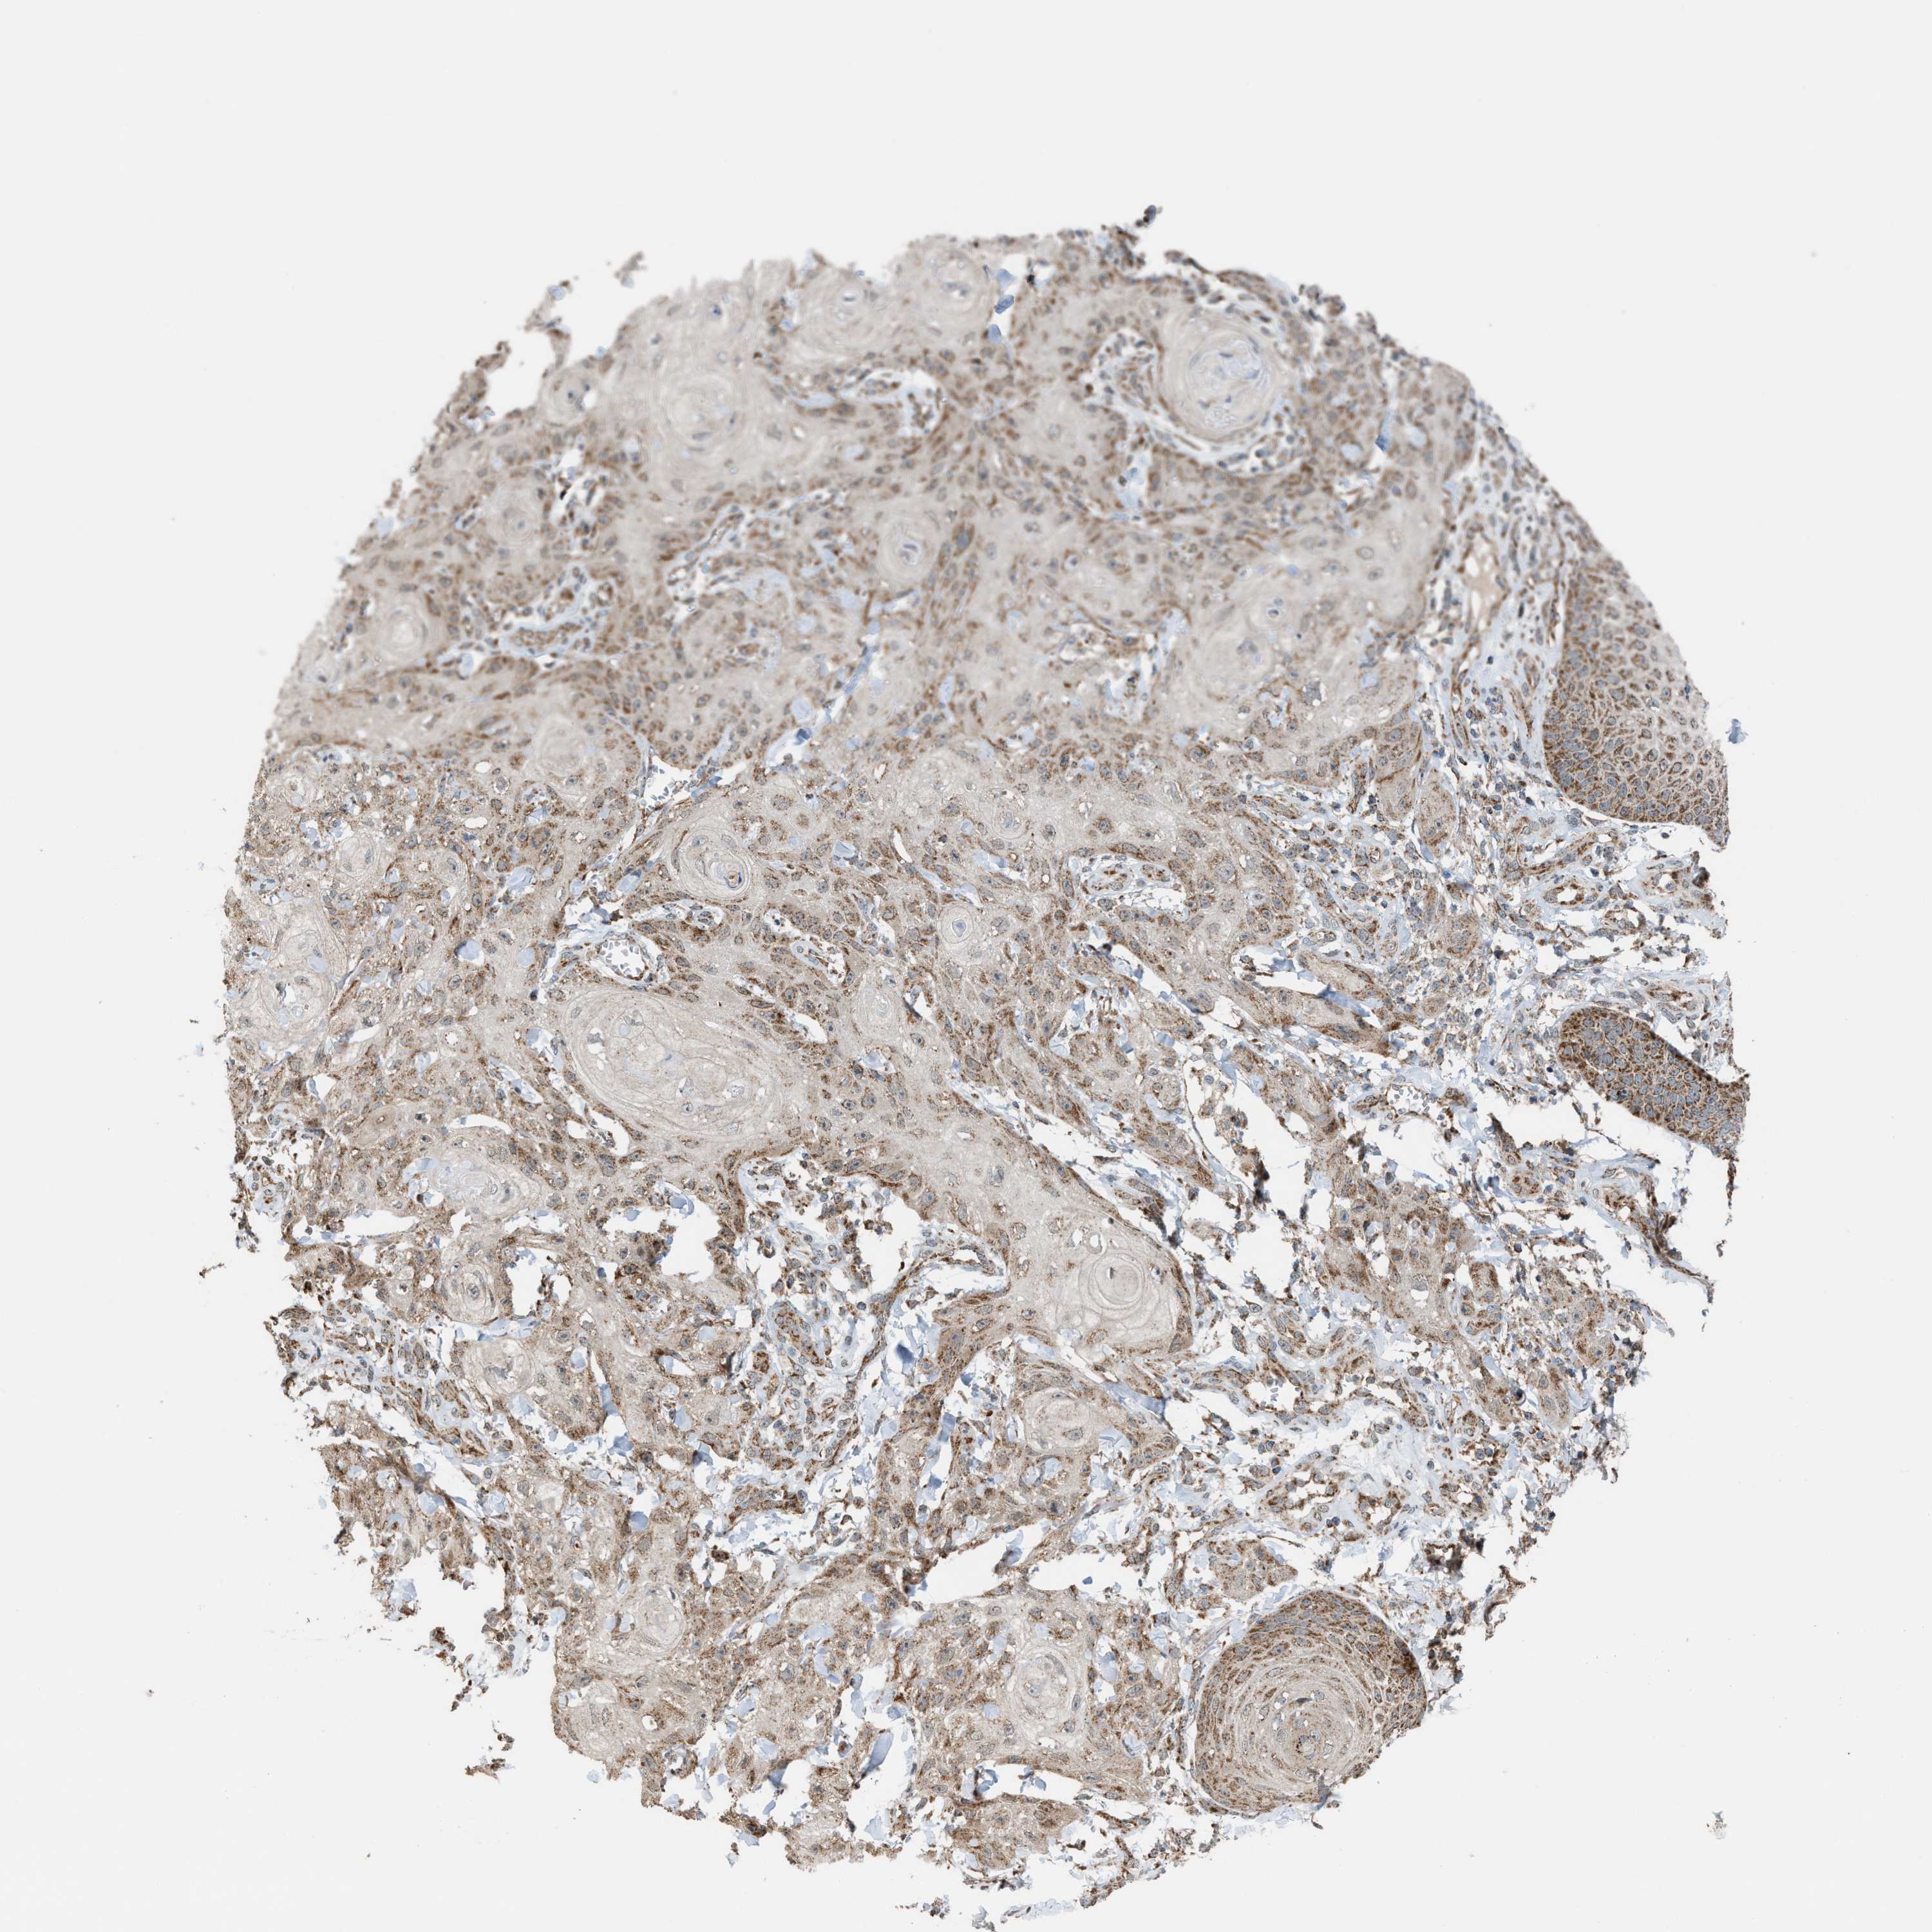

SKIN CANCER - Protein expressioni

A mouse-over function shows sample information and annotation data. Click on an image to view it in a full screen mode. Samples can be filtered based on level of antibody staining by selecting one or several of the following categories: high, medium, low and not detected. The assay and annotation is described here.

Each image is clickable and will lead to virtual microscopy that enables deeper exploration of all samples and also displays staining intensity scores, fraction scores and subcellular localization as well as patient and tissue information for each sample.

Antibody HPA021641

Staining

Medium

Intensity

Moderate

Quantity

75%-25%

Location

Cytoplasmic/membranous

Squamous cell carcinoma, metastatic, NOS